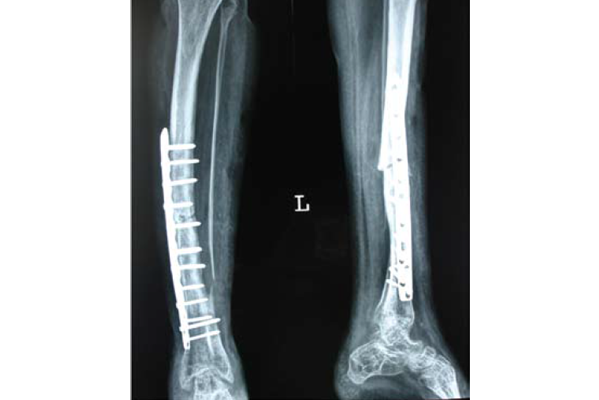

Pseudoarthrosis Tibia